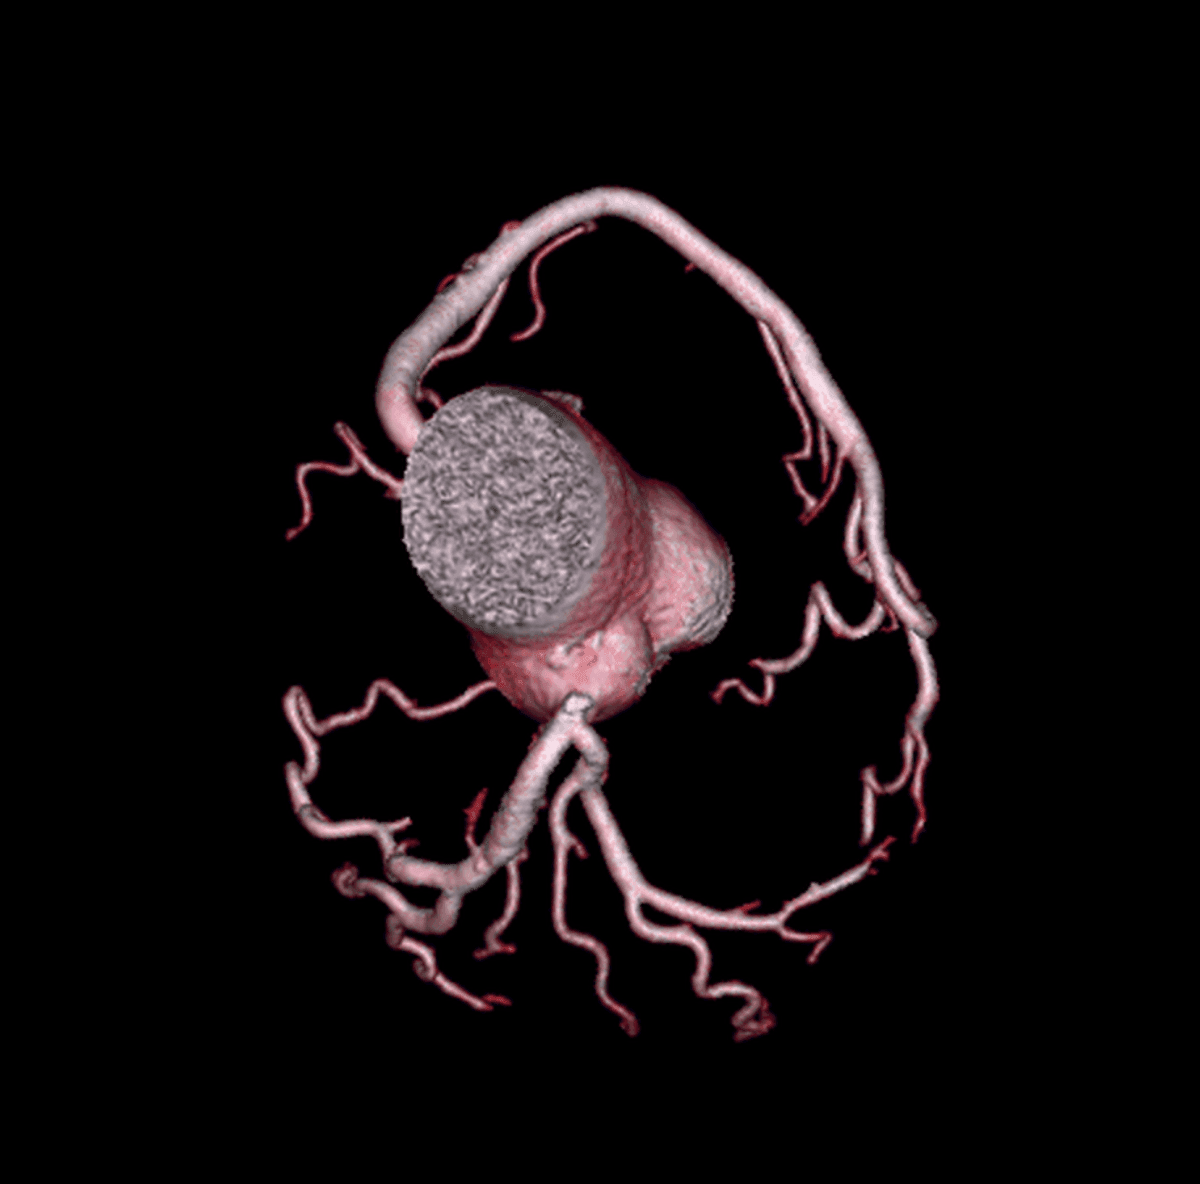

O que vemos nessa imagem???↓↓↓↓↓↓Resposta:O aneurisma do seio de Valsava é uma condição rara, que geralmente só causa sintomas após sua ruptura. É ocasionado pela separação ou pela falta de fusão e…